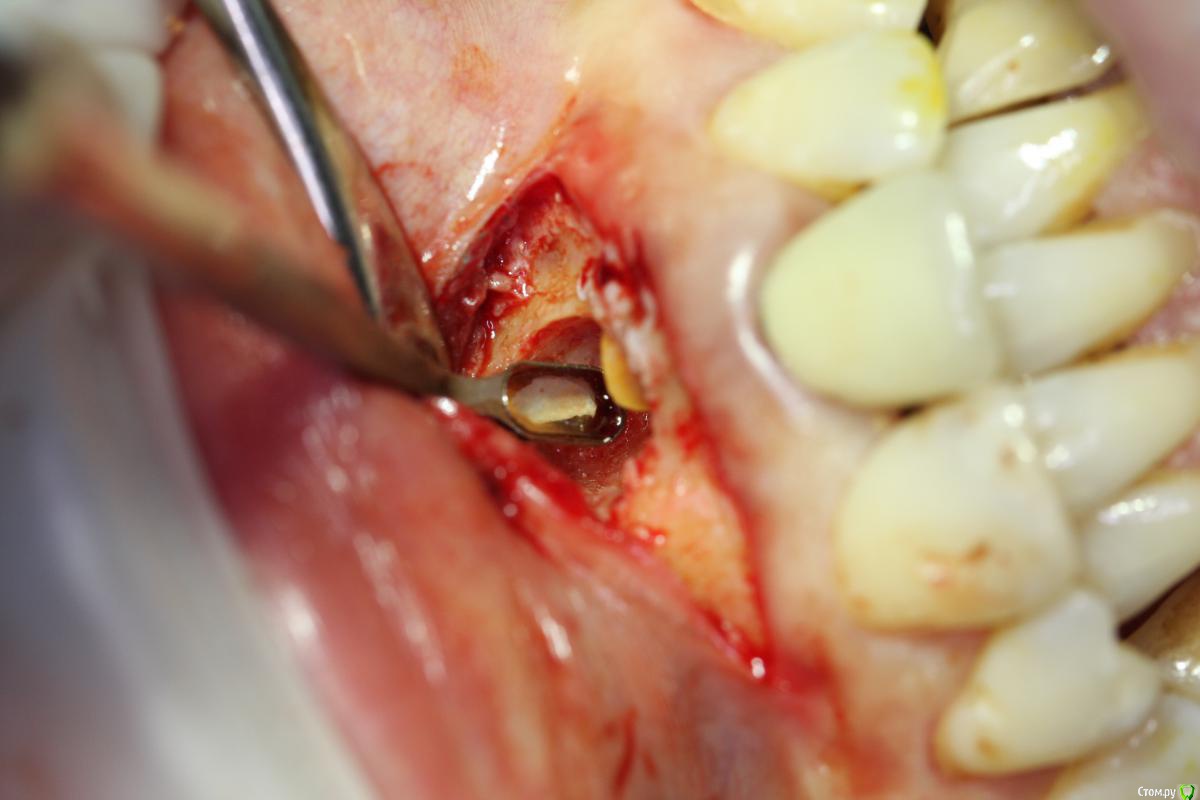

Zorrro Опубликовано 31 мая, 2016 Поделиться Опубликовано 31 мая, 2016 Во время резекций иногда хорошенько заливает,коагулятор у меня не всегда решает этот вопрос,как и ватные шарики с адреналином…Хочу с вами поделиться тем,что мне взбрело в голову,может кому-то пригодится.Взяв проавтоклавируемую фум ленту ,утрамбовал её с помощьюгладилки на дно полости.Кровотечение остановилось,позволив мне высушить зуб перед ретроградной пломбировкой. 13 Ссылка на комментарий